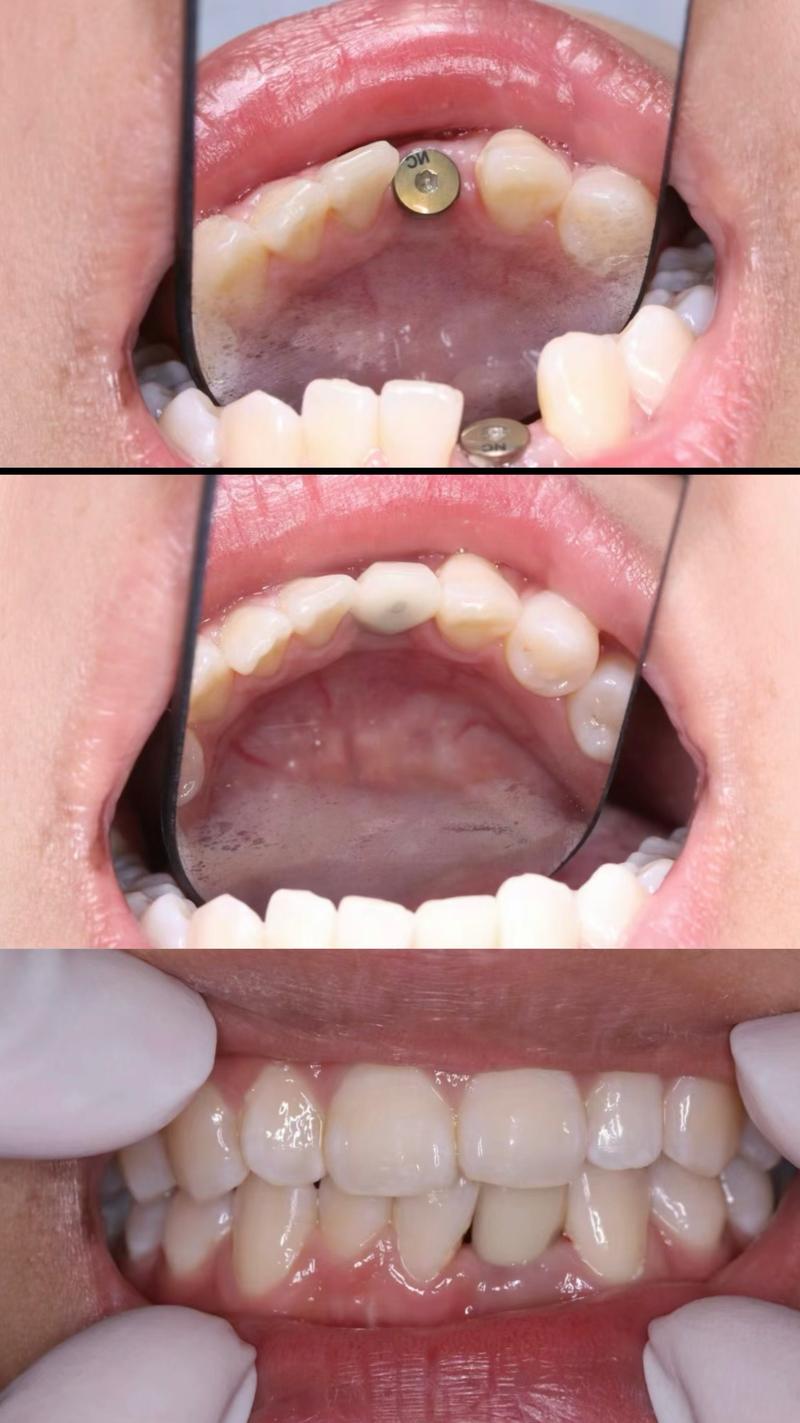

种牙流程与正畸的衔接

正畸拔牙后再种牙的治疗流程需严格遵循“先正畸、后种牙”的原则,即确保正畸治疗结束,牙齿排列整齐、咬合关系稳定后再进行种植手术,具体流程包括:①正畸结束与保持:拆除矫治器后需佩戴保持器1-2年,防止牙齿复发移位,同时观察牙槽骨的稳定情况;②种植手术:在局部麻醉下,逐级备洞后将种植体植入牙槽骨,缝合伤口,术后需注意口腔卫生,避免感染;③骨结合期:种植体植入后需等待3-6个月,与牙槽骨形成稳定的骨结合(即“骨整合”),期间避免种植体承受过大咬合力;④修复阶段:骨结合完成后,安装基台,取模制作牙冠,试戴调整后完成最终修复,恢复牙齿形态与功能。